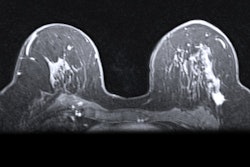

Although both MRI and ultrasound are capable of effectively imaging BI-RADS 3 lesions, each modality has respective differences in imaging features, which can be confusing for radiologists and clinicians to interpret. Arian and colleagues wanted to present MRI features of ultrasound-detected BIRADS-3 lesions and compare findings from both modalities among women with ultrasound-detected BIRADS-3 masses.

They looked at data from 123 ultrasound-detected BI-RADS 3 lesions in 67 patients with a median age of 38 years. The women who were focused on for the study included candidates of assisted reproductive therapy and patients with prior high-risk lesions.

The researchers found that MRI agreed with ultrasound on 87% (n = 107) of cases. MRI downgraded another 12 cases (9.8%) to BI-RADS 2 and upgraded four cases (3.3%) to BI-RADS 4.

Additionally, the median size of the lesions was 9 mm in MRI and 9 mm in ultrasound, which the team wrote was "highly" correlated, yielding a Spearman correlation coefficient of 0.889 (p < 0.001).

The group also found that MRI evaluation revealed two cases of deep lesions that were missed in ultrasound imaging.